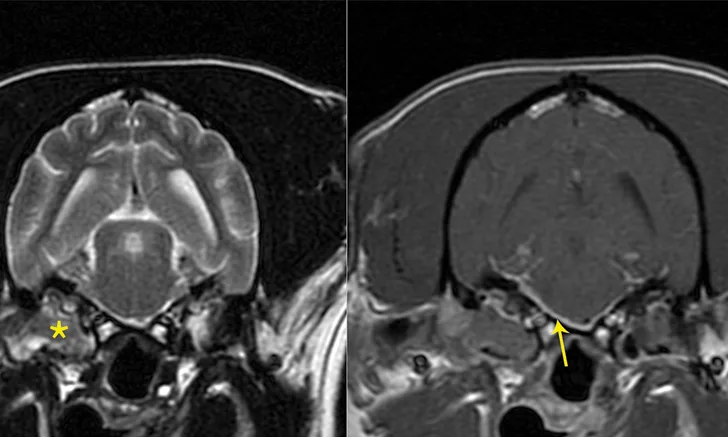

Contrast and post-contrast MRI images with markings denoting lesions in right middle ear extending into calvarium.

FIGURE 2

Transverse T2-weighted (left) and post-contrast T1-weighted (right) images obtained from a cockapoo with sudden onset of right peripheral vestibular dysfunction and right-sided facial paralysis. MRI showed right (*) worse than left middle ear disease with extension into the calvarium (otogenic meningitis; arrow) and into the right horizontal ear canal. Neutrophilic pleocytosis was present in the CSF (no bacteria seen on direct examination; CSF culture negative). The patient was treated with oral clindamycin for 1 month to reduce the intracranial portion of infection, and then right total ear canal ablation and lateral bulla osteotomy was performed. The histologic diagnosis for the tissue in the tympanic bulla was cholesteatoma, and bacterial culture identified secondary Staphylococcus pseudintermedius infection. The antibiotic was changed to amoxicillin-clavulanate based on antibiotic sensitivity testing.